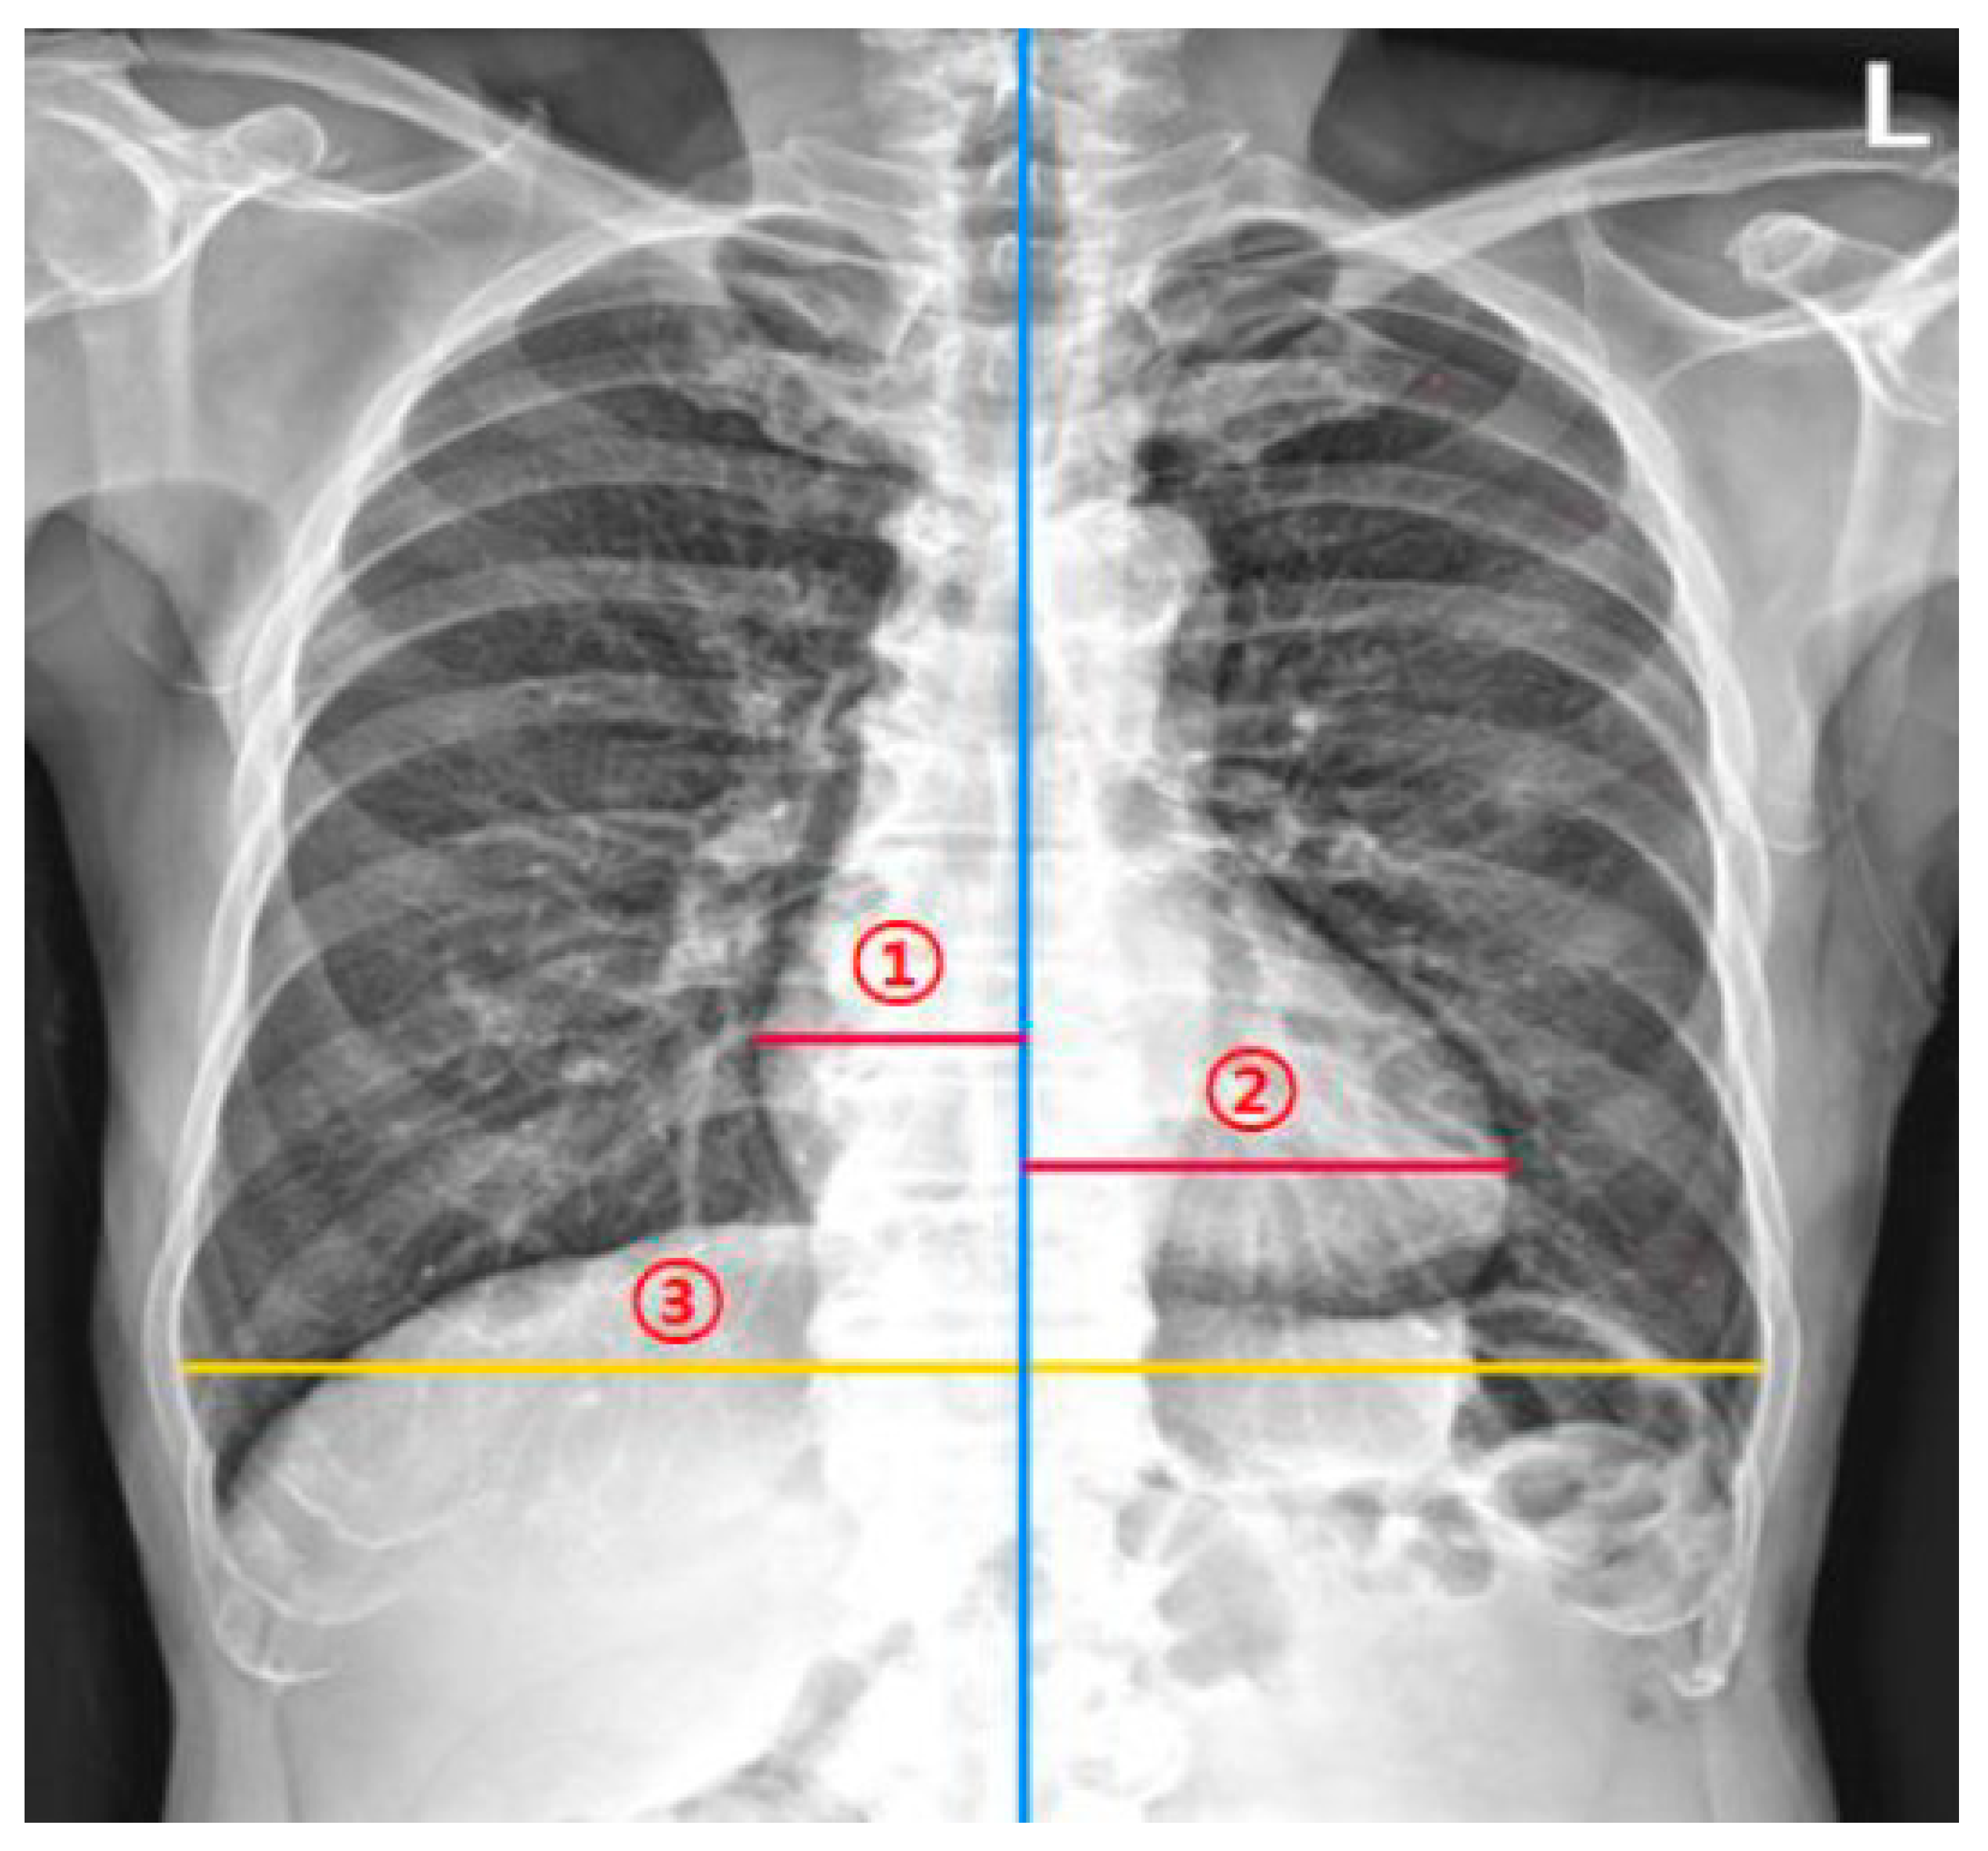

To assess the agreement between the DL model and human experts in measuring the CTR on chest radiographs, two thoracic radiologists measured the CTR of the 160 study sample radiographs. They independently measured the CTR twice at a 1-month interval (washout period). That is, four datasets for testing were obtained (two datasets from each of the two thoracic radiologists). When measuring the CTR, they were instructed to measure the maximum left heart diameter (MLD), the maximum right heart diameter (MRD), and the greatest transverse dimension of the thoracic cavity (GT). Then, the CTR was calculated as (MLD + MRD)/GT (Figure 2).

Figure 2.

Measurement of the cardiothoracic ratio (CTR). The CTR measurement model and radiologists measured (1) the maximum left heart diameter, (2) the maximum right heart diameter, and (3) the greatest transverse dimension of the thoracic cavity. The CTR is calculated as (maximum left heart diameter + the maximum right heart diameter)/the greatest transverse dimension of the thoracic cavity.